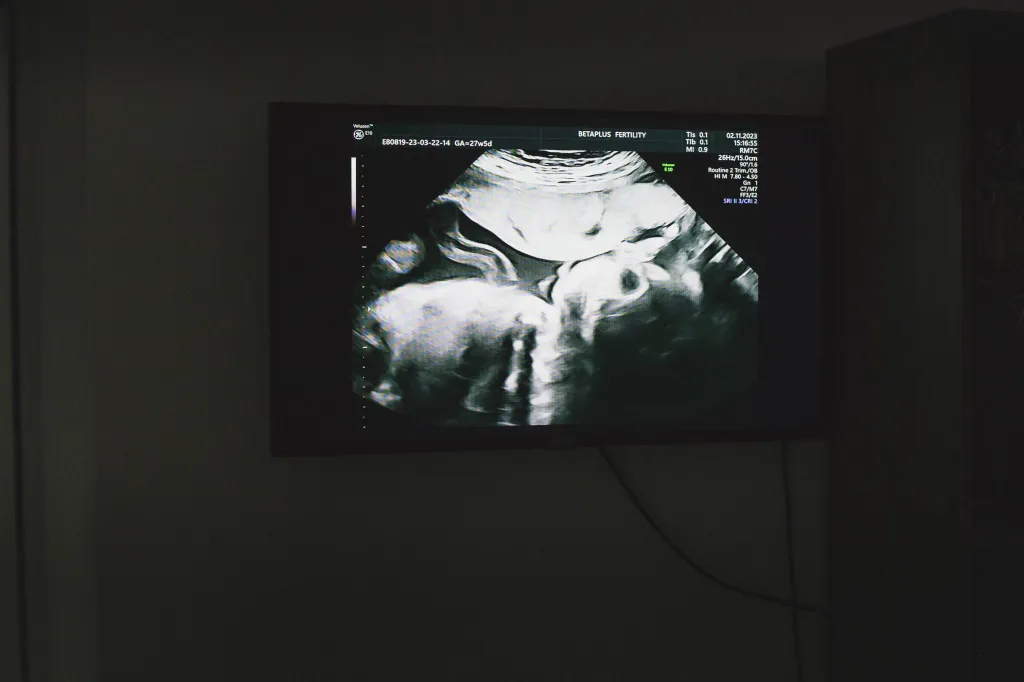

2024年11月2日,格鲁吉亚第比利斯,New Life 代孕机构营运的生育诊所,除了分娩以外所有医疗程序都在这里进行。摄:Marie Audinet/Hans Lucas/AFP via Getty Images